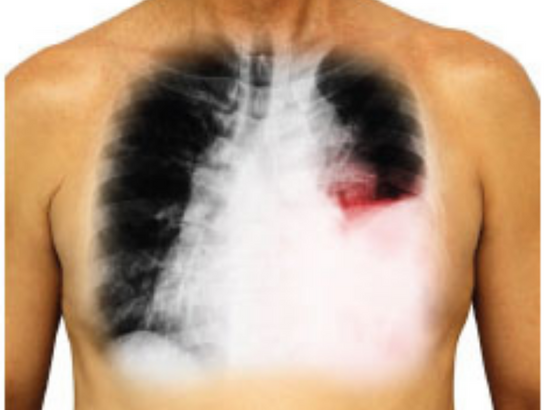

Pleural effusion, characterized by the accumulation of excess fluid between the pleura layers outside the lungs, can cause symptoms like shortness of breath, chest pain, fever, and cough. Dr. Himabindu at Helios Lung Care, the best pulmonologist in Kondapur, evaluates patients with symptoms and a medical history.

To diagnose pleural effusion, Dr. Himabindu performs tests such as chest X-rays, CT scans, and ultrasounds. Thoracentesis, involving fluid removal for analysis, and Pleural fluid analysis are crucial diagnostic procedures.